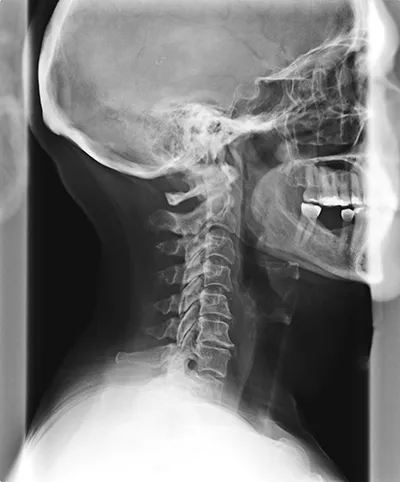

Spinal Degeneration Phase I

The first phase of spinal degeneration is characterized by changes in spacing between the spinal discs. There are usually no obvious symptoms of phase I, and it usually isn’t painful. Phase I degeneration, if not corrected, will eventually lead to more degeneration and more health problems.